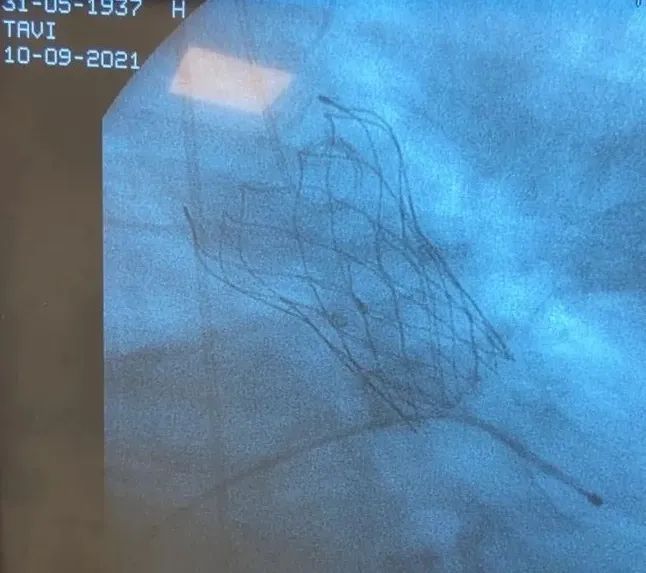

手术过程非常顺利,已经是第二次使用VitaFlow®的Matias Sztejfman医生带领团队驾轻就熟,采用24mm Alwide®球囊预扩后,VitaFlow®输送系统轻松过弓。调整输送系统位置和深度后,VitaFlow®的电动手柄保证精确释放,最终瓣膜植入深度2mm,血流动力学结果显示零压差,极微量反流。心电图未见传导阻滞。

植入后结果